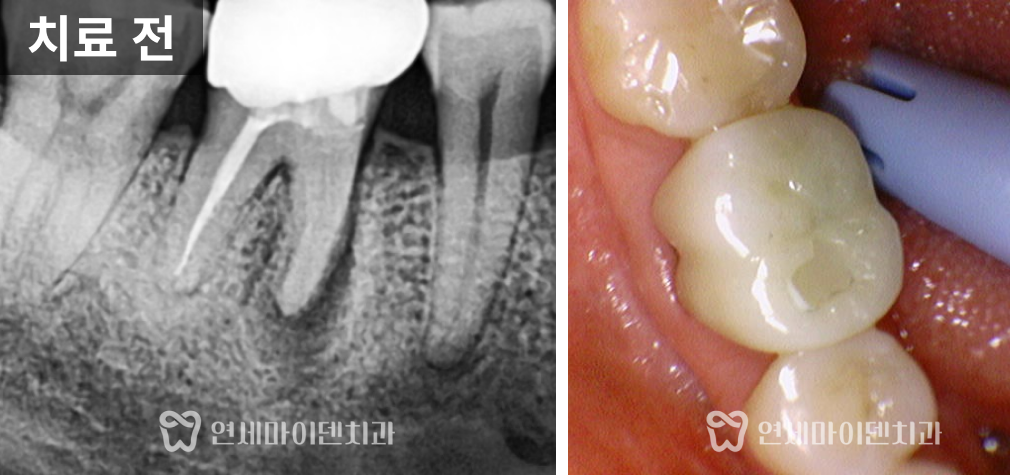

이 환자분은 '예전에 신경치료를 받았던 왼쪽 위 어금니쪽이 시린 증상이 있고 아프다'며 내원하셨는데요.

두 개의 치아 모두 불편함이 있었고, 모두 치료를 받은 지 꽤 되었으며, 염증이 있는 상태였습니다.

살펴보니 과거에 받으셨던 신경치료의 퀄리티가 아쉬운 부분이 있었습니다.

신경관뿌리까지 치료가 되어있지 않고, 중간에 갭이 보였습니다.

치료를 조금만 하면 개선의 여지가 있겠다는 생각이 들어, 우선은 재신경치료를 하기로 했습니다.